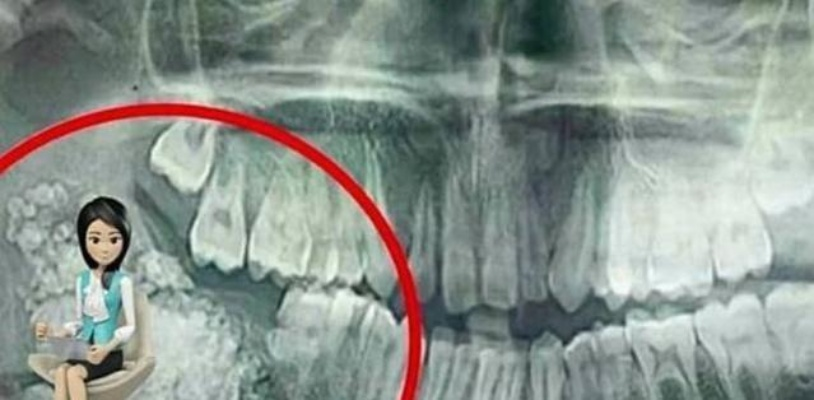

魏馨团队给出的方案让她破涕为笑:经脐单孔腹腔镜手术,这种手术的“巧思”在于利用肚脐的天然褶皱——肚脐是出生后脐带脱落的凹陷,本身就是身体的“隐蔽区”,医生只在肚脐上开一个2厘米的切口,把腹腔镜和器械从这里伸进去,像“拆精密快递”一样小心剥离肿瘤,手术结束时,护士清点肿瘤内容物,连见多识广的医护都惊讶:里面竟有24颗形态各异的牙齿,有的像乳牙般细小,有的已经长出牙根,还有一块直径5厘米的骨骼。